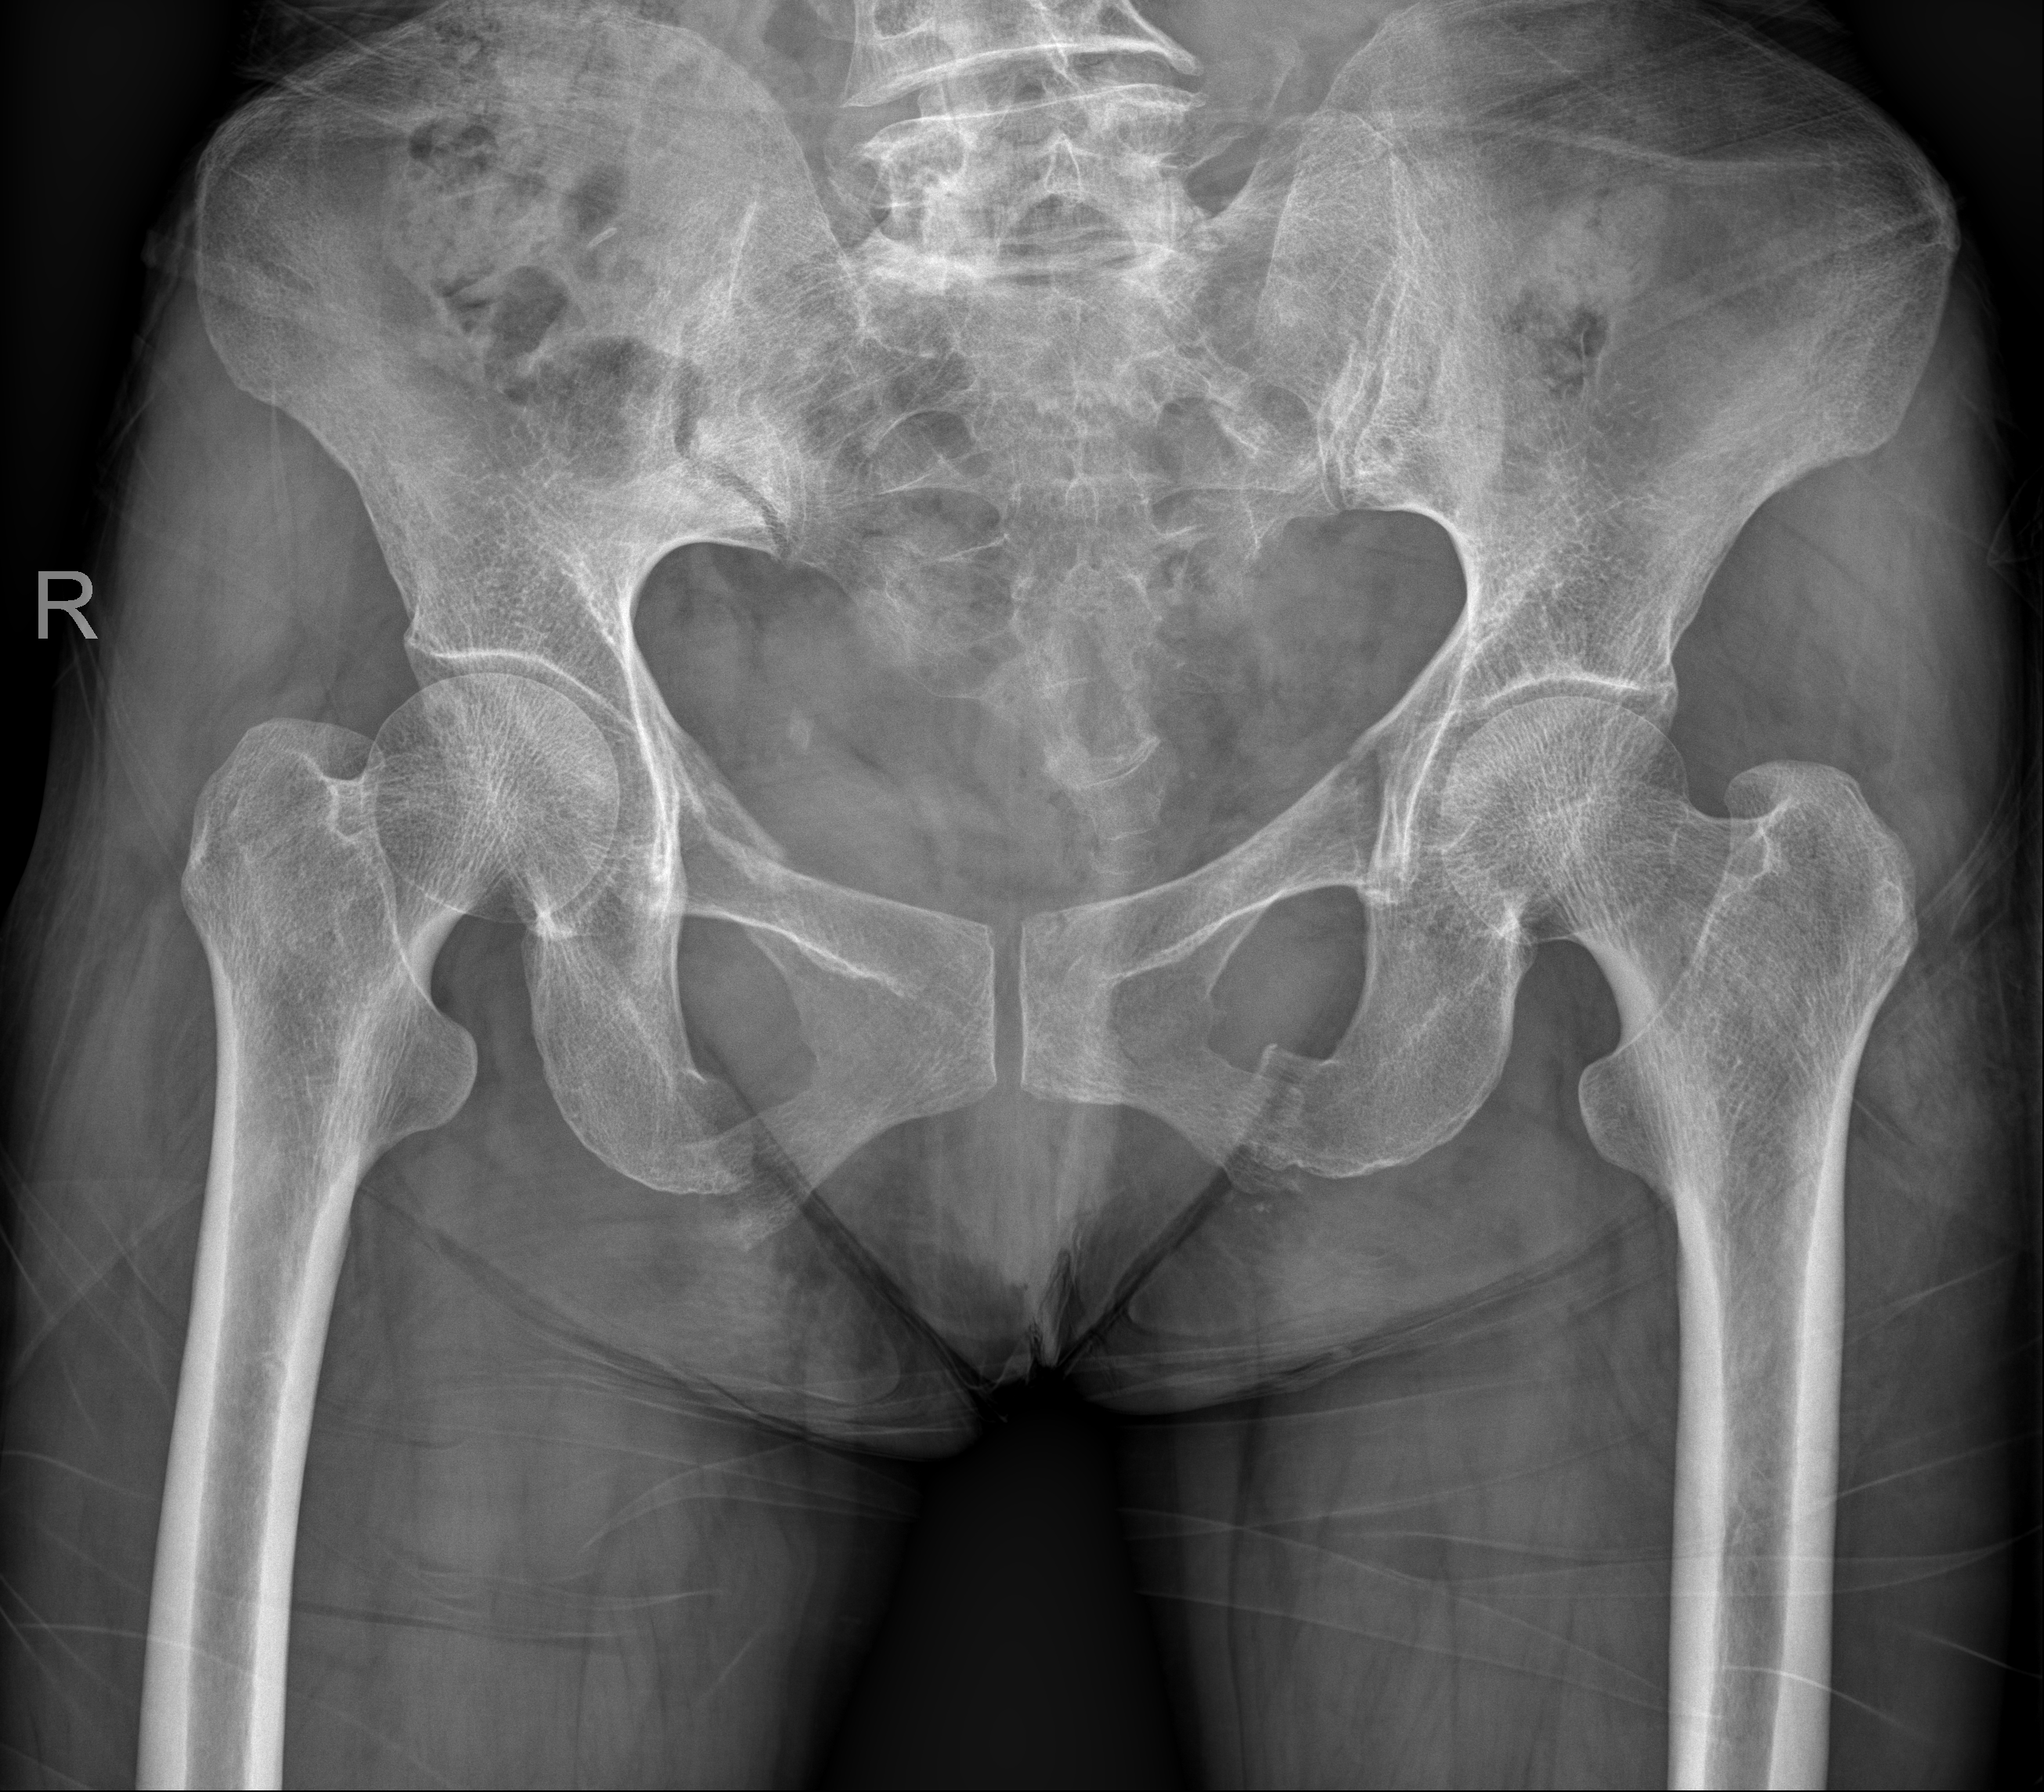

术前